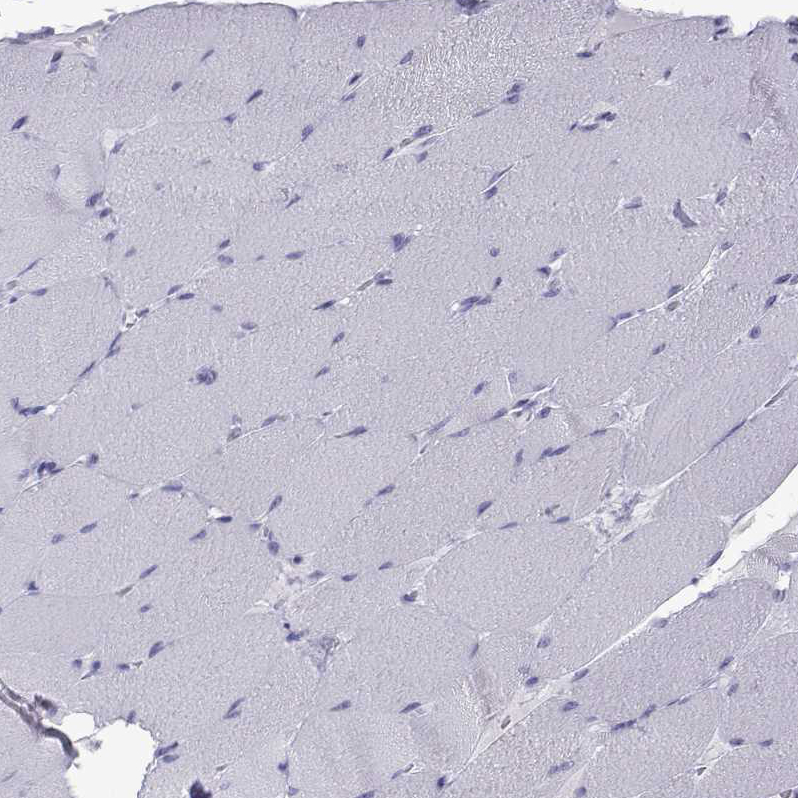

Immunohistochemistry analysis in human testis and skeletal muscle tissues using HPA021624 antibody. Corresponding ACTL7A RNA-seq data are presented for the same tissues.